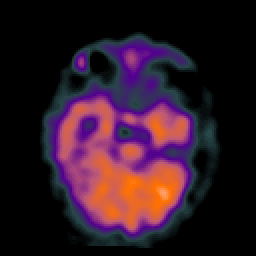

Hypertensive Encephalopathy, overlay -- Slice #8

[Home][Help][Clinical] Slice 8